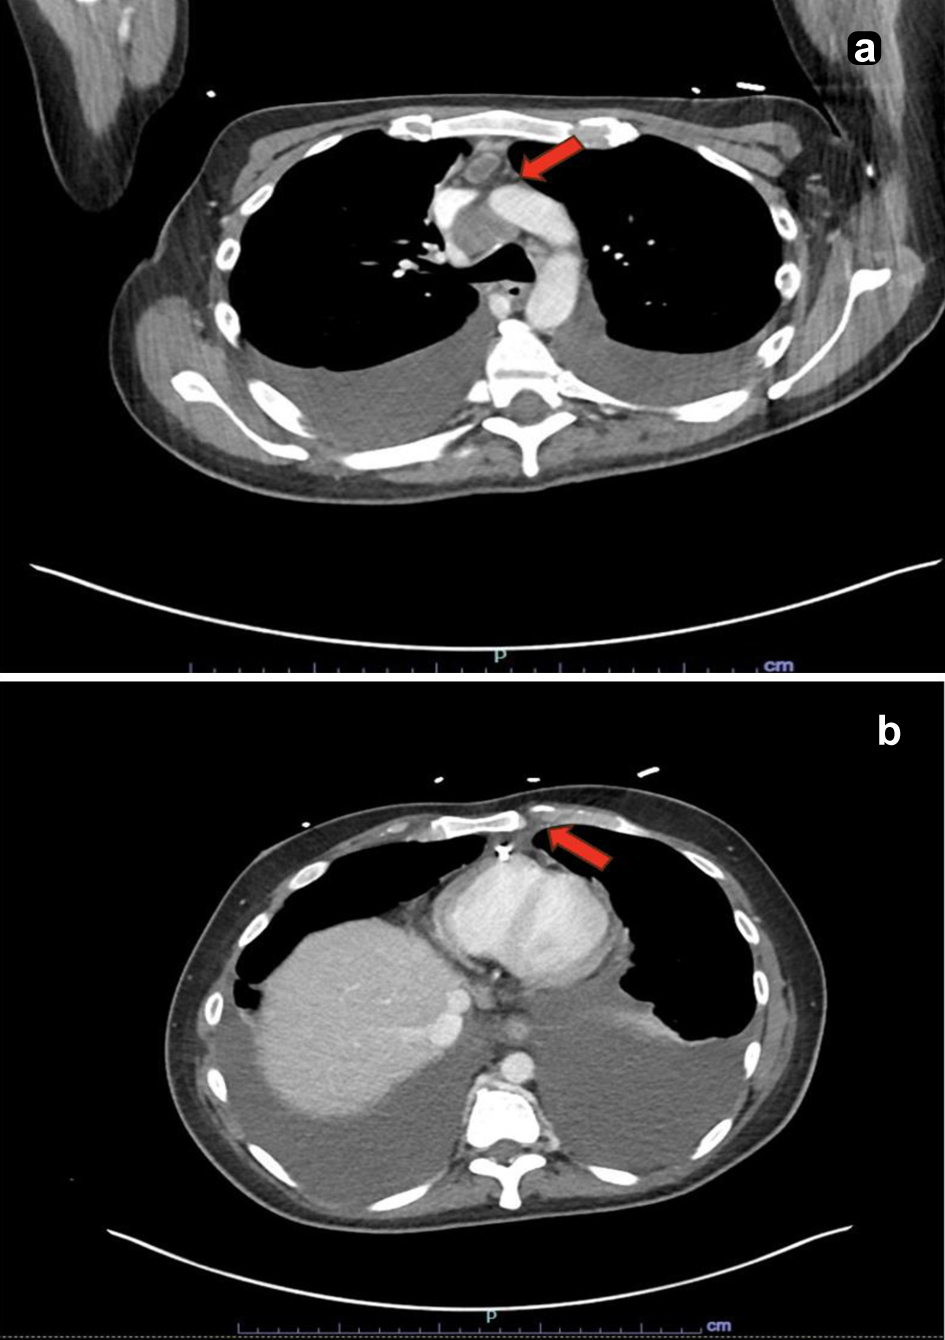

Due to elevated D-dimer (12.69 µg/mL FEU) and worsening respiratory status, computed tomography (CT) pulmonary angiogram was performed, ruling out pulmonary embolism but revealing right pleural effusion, pericardial effusion, a pulmonary nodule, nodular peritoneal thickening, omental infiltration, and extensive mediastinal and retroperitoneal lymphadenopathy (Figs. 1 and 2), suggestive of metastatic malignancy or granulomatous disease. Thoracentesis yielded 1.2 L of serosanguinous fluid, with analysis notable for exudative characteristics: total cell count 1,079 × 106/L (17% neutrophils, 55% lymphocytes), glucose 75 mg/dL, pH 7.57, lactate dehydrogenase 634 U/L, protein 4.4 g/dL, red blood cell (RBC) 12 × 106/L, and elevated adenosine deaminase (ADA) at 48 U/L. Initial microbiological studies, including M. tuberculosis polymerase chain reaction (MTB-PCR), Gram stain, bacterial and fungal cultures, and acid-fast bacilli (AFB) smears, were negative. Subsequent labs were notable for metabolic disturbances (persistent hypocalcemia, hypoglycemia, hypomagnesemia), undetectable vitamin D (< 3.5 ng/mL), and elevated inflammatory markers (C-reactive protein 3.62 mg/dL and lactate 3.2 mmol/L). Malignancy markers (carbohydrate antigen 19-9 (CA19-9), carcinoembryonic antigen (CEA), and alpha-fetoprotein (AFP)) were unremarkable.

Figure 2. Computed tomography scan of the chest. (a) Enlarged lymph node within the anterior mediastinum measuring up to 1.0 cm in the short axis with central hypodensity concerning for necrosis (red arrow). (b) An enlarged retro-crural lymph node measuring up to 0.9 cm in the short axis (red arrow).